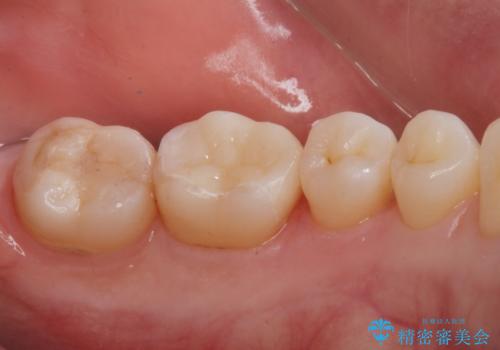

e-maxインレーはセラミックの詰め物の事です。

セラミックは銀の詰め物に比べて虫歯になりにくい性質があります。

白い詰め物が入り、大変満足して頂けました。